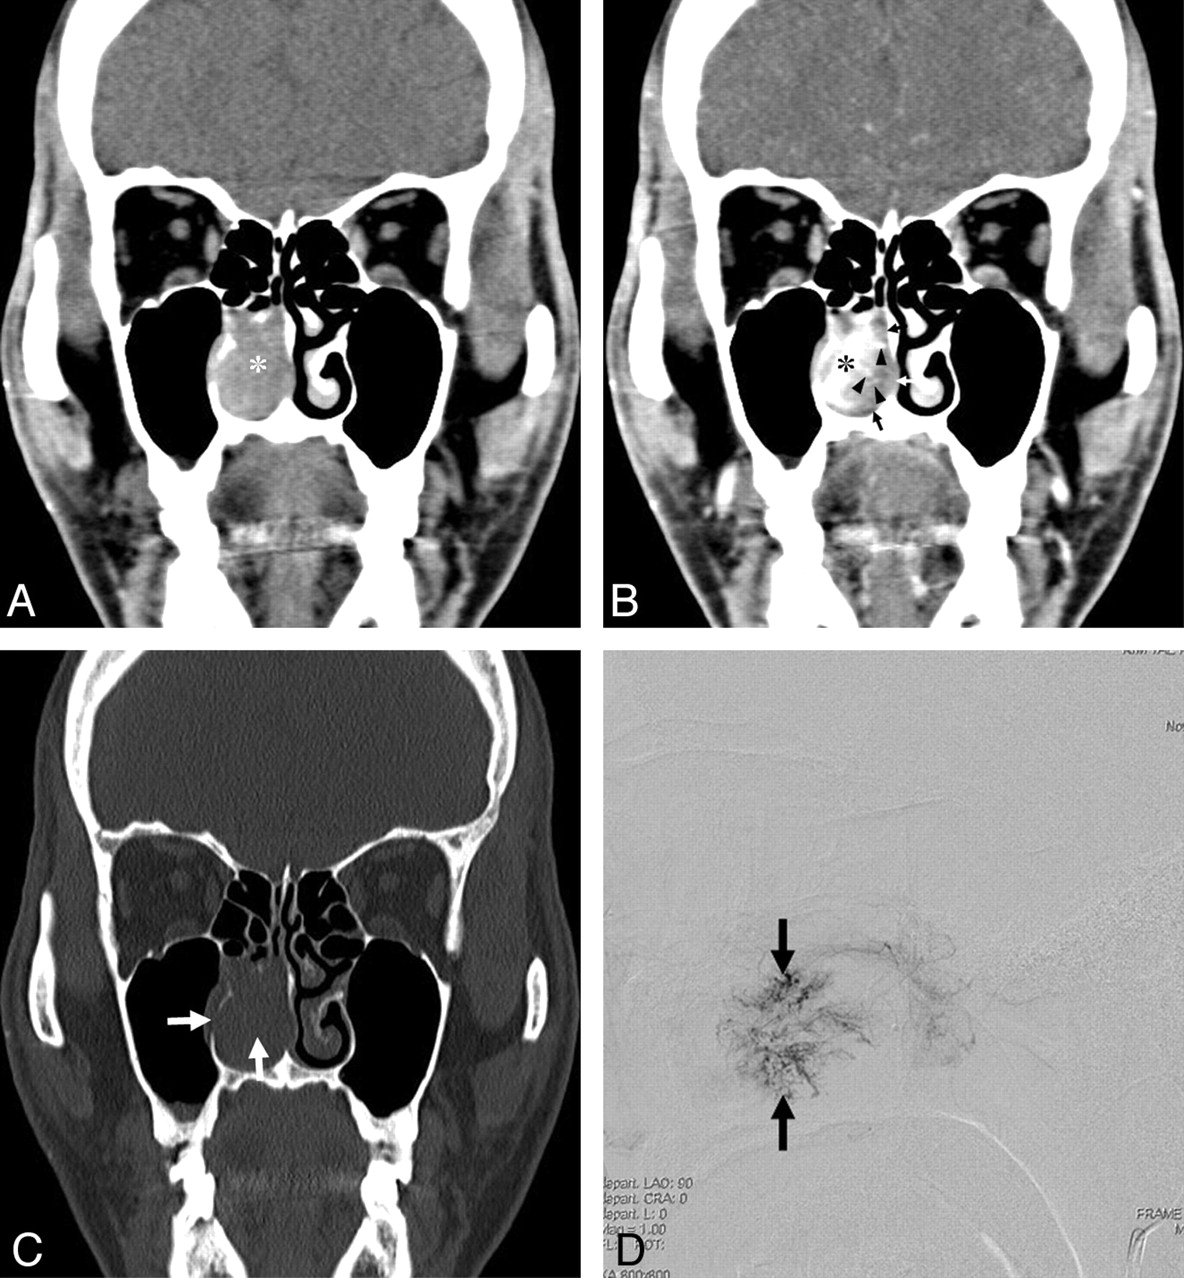

કોન્ટ્રાસ્ટ CT સ્કેનથી જાણવા મળ્યું કે આ રચના રક્તવાહિનીઓની જાળ જેવી ગૂંચથી બનેલી છે. નેસલ સેપ્ટમમાં આવી રચના દેખાવું અત્યંત દુર્લભ હોવાથી, ડૉ. ઠક્કરે ખાસ કાળજીપૂર્વક એન્ડોસ્કોપિક સર્જરી કરવાની યોજના બનાવી. સચોટ નિદાન બાદ ઓપરેશન ખૂબ ધ્યાનપૂર્વક કરવામાં આવ્યું અને ટ્યુમરને સંપૂર્ણપણે દૂર કરવામાં આવ્યું. બાયોપ્સી રિપોર્ટમાં પુષ્ટિ થઈ કે આ લીઝન Anastomosing Hemangioma છે, જે બિન-કેન્સરજન્ય પરંતુ અત્યંત દુર્લભ પ્રકારનું વાસ્ક્યુલર લીઝન છે.